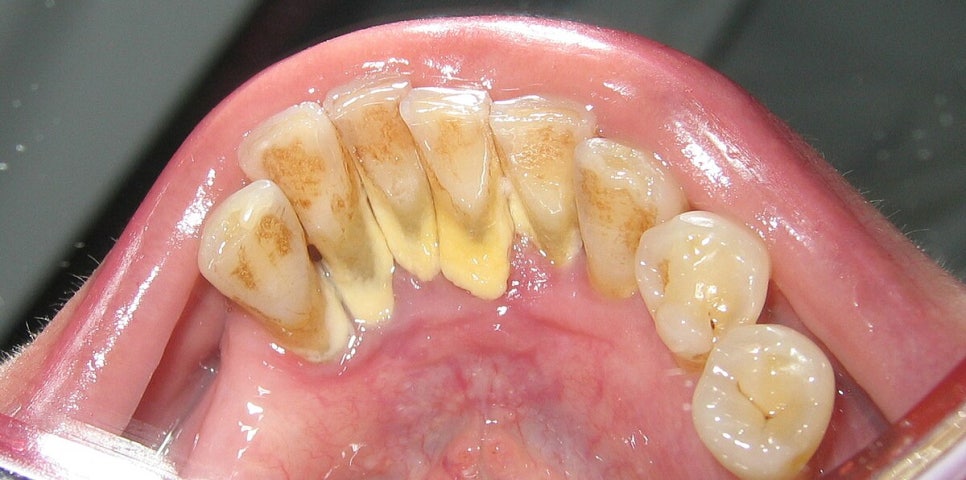

입냄새의 가장 흔한 원인 중 하나는

바로 치석/치태입니다.

치태(plaque)는

양치 후에도 남아 있는 세균 덩어리이고,

이게 굳으면 치석(calculus)이 됩니다.

문제는 이 치석과 치태가

잇몸 가장자리에 오래 머물면서

잇몸 염증(gingivitis)을 만들고,

그 과정에서 입냄새의 원인이 되는

황화합물(VSCs)을 만들어낸다는 점이에요.

치석은 단순한 ‘딱딱한 때’가 아닙니다.

그 표면은 울퉁불퉁해서

세균이 더 잘 달라붙는 구조예요.

그래서 치석이 있으면

잇몸이 쉽게 붓고

양치할 때 피가 나고

눌렀을 때 묵직한 통증이 생깁니다.

치태가 점점 쌓여 굳으면 치석이 됩니다. 그 치석은 표면이 울퉁불퉁하고 혐기성 성질을 띠어서 세균이 서식하기 좋은 환경이 되죠. (출처: https://www.thomsonmedical.com)